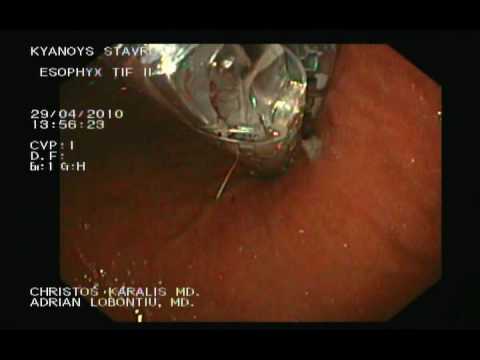

Esophyx - Endoskopowa Fundoplikacja, Cz. 1.

Refluks żołądkowo-jelitowy (GERD) manifestuje się przewlekłym zapaleniem przełyku, przełykiem Barrett'a a także rakiem. Czasem pojawia się również przepuklina rozworu przełykowego. Chirurgia i fudoplikacja...

Esophyx - Endoskopowa Fundoplikacja, Cz. 2.

Refluks żołądkowo-jelitowy (GERD) manifestuje się przewlekłym zapaleniem przełyku, przełykiem Barrett'a a także rakiem. Czasem pojawia się również przepuklina rozworu przełykowego. Chirurgia i fudoplikacja...

Esophyx - Endoskopowa Fundoplikacja, Cz. 1.

Refluks żołądkowo-jelitowy (GERD) manifestuje się przewlekłym zapaleniem przełyku, przełykiem Barrett'a a także rakiem. Czasem pojawia się również przepuklina rozworu przełykowego. Chirurgia i fudoplikacja...

Esophyx - Endoskopowa Fundoplikacja, Cz. 3.

Refluks żołądkowo-jelitowy (GERD) manifestuje się przewlekłym zapaleniem przełyku, przełykiem Barrett'a a także rakiem. Czasem pojawia się również przepuklina rozworu przełykowego. Chirurgia i fudoplikacja...